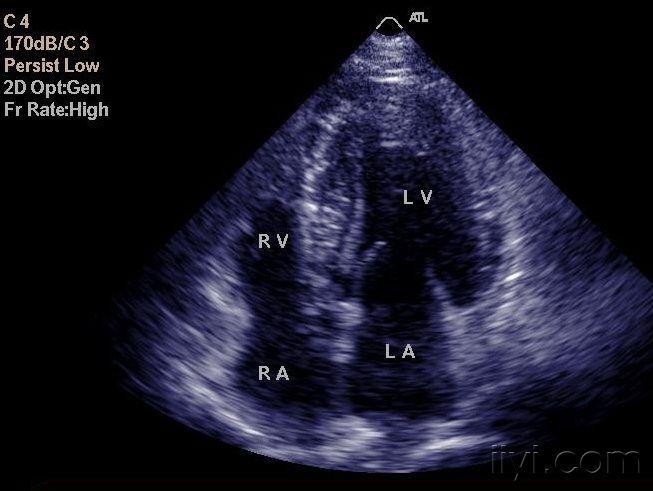

肥厚型心肌病超声图片,肥厚型心肌病心电图

第2节 肥厚型心肌病

肥厚型心肌病?梗阻还是非梗阻?

【原创】肥厚性非梗阻型心肌病